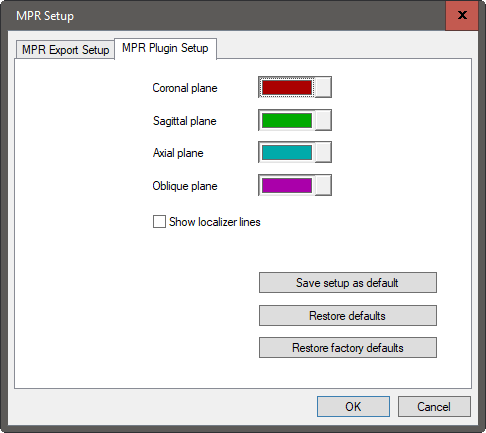

A MPR beépülő modul beállítása

Az ortogonális képkockák színeinek beállításai az MPR beépülő modul beállítása oldalon konfigurálhatók. Ezen az oldalon a felhasználó meghatározhatja a kívánt színt, és engedélyezheti vagy letilthatja a színkoordinált lokalizáló vonalakat.